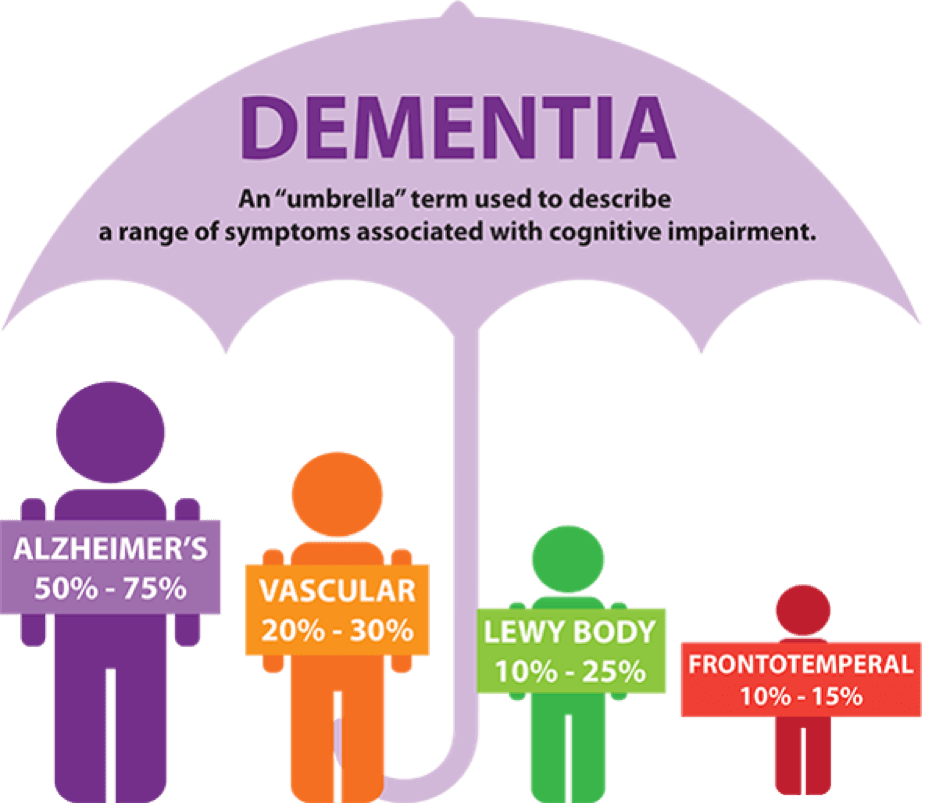

Dementia is an umbrella term. It describes the symptoms that occur when …

Dementia

Dementia 101: Know the Different Types of Dementia

What is Dementia? Dementia vs Alzheimer’s Disease